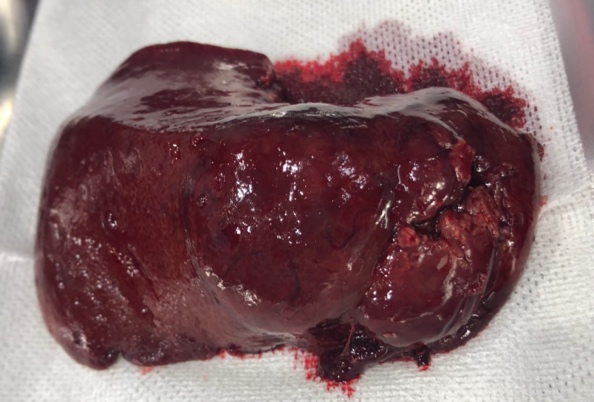

肝臓腫瘍

臨床症状は非特異的なことが多いが、血液検査における肝酵素値の上昇や、稀に腹水や黄疸などの症状を示します。

犬では肝細胞癌が最も多く、胆管腫瘍、神経内分泌腫瘍、間葉系腫瘍なども認められます。猫ではリンパ腫や、胆管の癌が多いです。

孤立性の肝臓腫瘍の症例では外科的切除が推奨される治療法であり、外科的に切除可能な場合は予後が大きく改善されます。